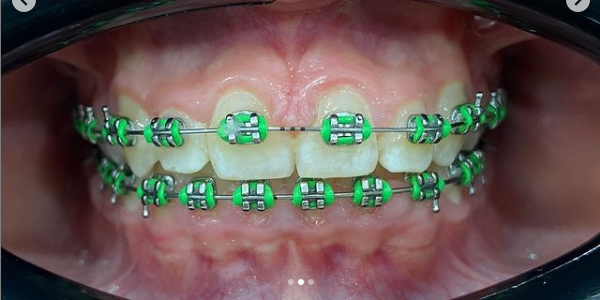

Установка брекетов

4 месяца назад пациентке были установлены брекеты Marquis.